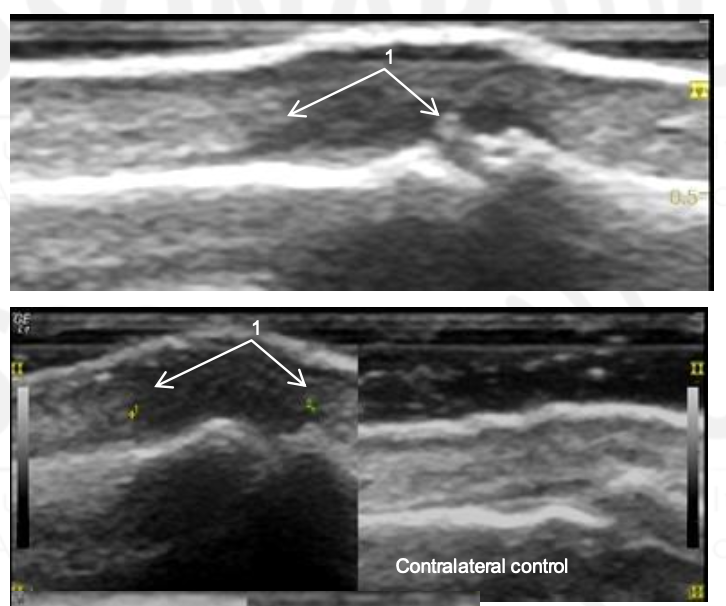

What is 1?

This is extensor calcification tendinopathy at the PIP.

What is 1 and 2?

CPPD at the MCP